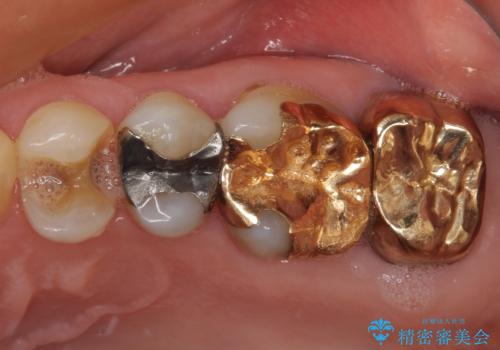

外れてしまった銀歯 セラミックインレーで自然な仕上がりに

- 奥歯の銀歯が外れてしまったため、セラミック治療を希望された患者様です。

セラミックインレーによる修復治療を実施しました。

正面から見える場所であったため、セラミックインレーで自然な口元にすることができました。